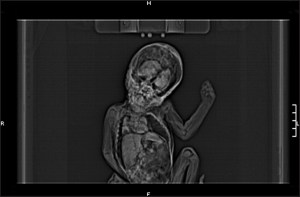

PX1Leo-scan_3106899b“I only wish more people could see the side of him that I do,” a friend of a famous person, stereotyped for being ultra-serious, says. “He’s actually, really very funny.” This friend will then go on to provide general information that characterizes a playful side of this famous person that most people don’t know. They may say something like, “Behind closed doors, he just has us in stitches. He loves children, and there’s nothing he loves more than watching a little kitten play with a ball of yarn.” This friend usually lays out the evidence of their friend’s silly side at a time when it is most beneficial for that politician, star, and/or actor to have a softer, more playful side added to their profile. The best case scenario for all involved is to simply float this trial balloon, and allow it to continue to float in the imaginations of the public. The alternative, of course, is to send that client out to provide the world some evidence, but this is usually fraught with danger, as what is considered funny by the loyalists and acolytes, that form the famous person’s entourage, may not play as well with those that don’t stand to benefit from believing that the person is funny.